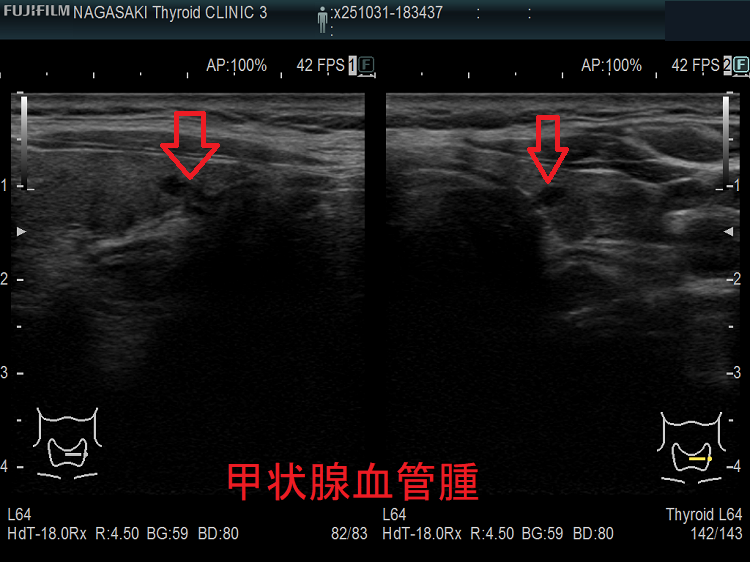

甲状腺に発生する血管腫は非常に稀で、日本の報告例もわずかです(日臨外会誌 72(3),579―583,2011)。

ケース①

ケース②

ケース③

甲状腺血管腫(拡大) ドプラーモード(eFlow);腫瘍内血管が3次元的に見え、毛玉の様。

ケース④